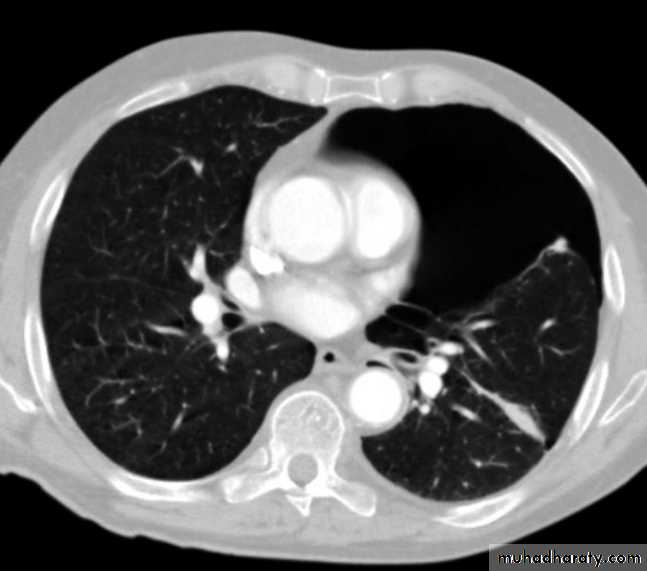

Pancreatitis

Patient present with abdominal pain , vomiting with or without jaundice , increase amylase level

CT finding

Enlargement of the pancreas focal or generalized increase in size .

Hypo density within the pancreas focal or generalized due to the edema .

Peri pancreatic fluid collection & edema around the pancreas .

The fluid around the pancreas if persist more than 6 w become encysted leading to the pancreatic pseudo cyst any area could be affected .

Edema of the wall of the stomach .

CT Scane